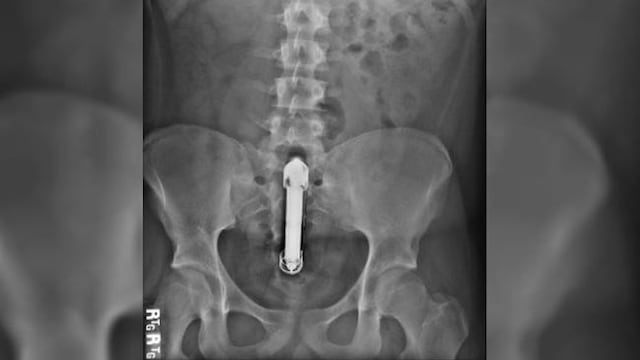

Al parecer, Nigel Willis, un hombre de 50 años, se sintió avergonzado y evitó visitar a un doctor tras tener en su cuerpo un vibrador atascado en su recto después de una noche de sexo. Lamentablemente este descuido lo llevó a un shock séptico que terminó enterrándolo 3 metros bajo tierra.

Willis permaneció 5 días con malestares y mareos. Pero su vergüenza pudo más que su salud, y tras varios intentos que realizaron sus amigos para convencerlo en visitar al doctor, finalmente Willis accedió, pero ya era demasiado tarde. La investigación reveló que los médicos encontraron que el juguete sexual había perforado su intestino, lo que lo llevó a un fallo multiorgánico, sepsis y una perforación en el intestino.